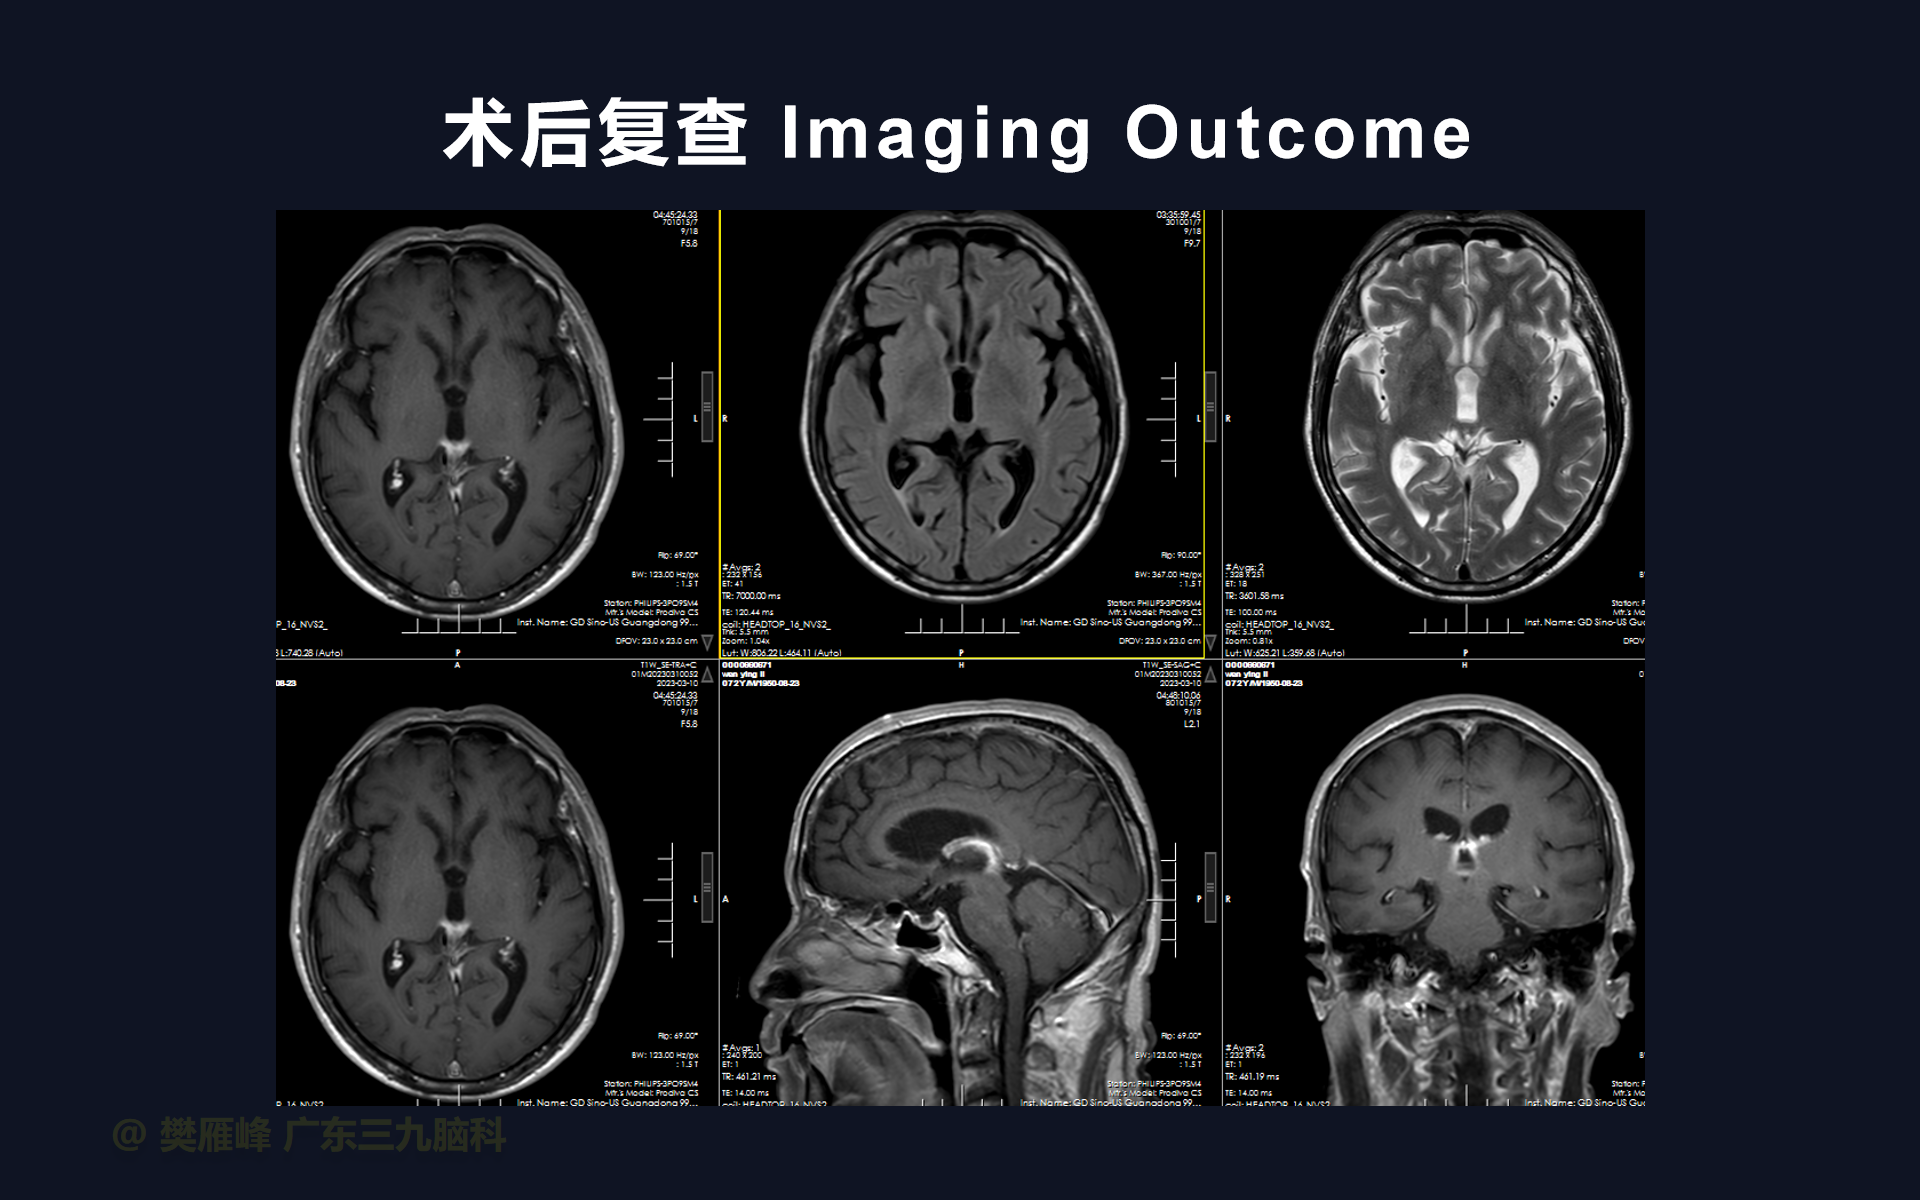

在这个二维手术视频中,展示了2例神经内镜下三脑室底造瘘+活检治疗三脑室后部肿瘤的方法。患者均为三脑室后部病变导致的梗阻性脑积水,病理结果1例为生殖细胞瘤,1例为淋巴瘤,在经过术后的放化疗病情均得到控制,生活质量满意。我们展示了安全的病变活检和第三脑室造瘘的技术要点,以最大限度减少术后继发脑积水和早期并发症。